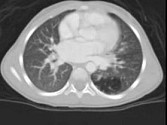

- 单项选择题女,2岁, 咳嗽,结合图像, 最可能的诊断是 ( )

A、先天性肺不张

B、细支气管肺炎

C、先天性支气管闭锁

D、先天性囊性腺瘤样畸形

E、肺隔离症